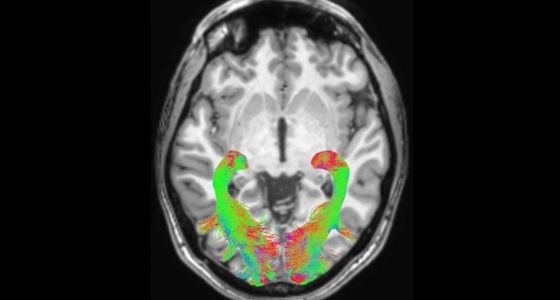

이 발견의 중심에는 작디작은 세포 하나가 있다. 마이크로글리아(microglia), 우리말로 '미세아교세포'라 불리는 이 꼬꼬마 세포가 그 주인공이다. 이 세포가 우리의 정신건강과 인지기능에서 핵심적인 역할을 맡고 있으며, 미래에 삶의 질을 혁신적으로 끌어 올릴 희망을 제시하고 있다.

그런데 다른 세포를 확인하려고 배양통을 들여다보거나 슬라이드를 올리면 미세아교세포가 꼭 끼어들었다. 그럴 때마다 뇌과학자들은 '짜증 나는 미세아교세포가 여기 또 있네!"라며 이를 갈곤 했다. 그만큼 미세아교세포는 수도 많고, 뇌 전체에 분포되어 있었다. 이 점에 의문을 품은 한 과학자가 이 세포를 파헤치기 시작한다.

베스 스티븐스는 미세아교세포에 주목했고, 뇌 과학에 혁명을 불러올 사실을 발견했다. 미세아교세포는 청소부가 아니라 보안요원이었다는 사실이다. 우리 몸에서 같은 역할을 하는 세포가 바로 백혈구다. 백혈구는 우리 몸속에 침입자가 들어오면 대식세포로 변해 이들을 잡아 먹어 몸 밖으로 배출하는데, 뇌에서는 그 역할을 미세아교세포가 담당하고 있었던 것이다.

그래서 평상시 미세아교세포는 뇌 속의 천사라고 할 수 있다. 이들은 뇌 신경망을 보호하는 단백질과 화학 분자들을 아낌없이 토해내며 시냅스 유실을 막으려고 최선을 다한다. 적재적소에 자양분을 분비하고 미엘린의 성장을 촉진하며, 우리 뇌의 신경세포를 보호하는 데 최선을 다한다.